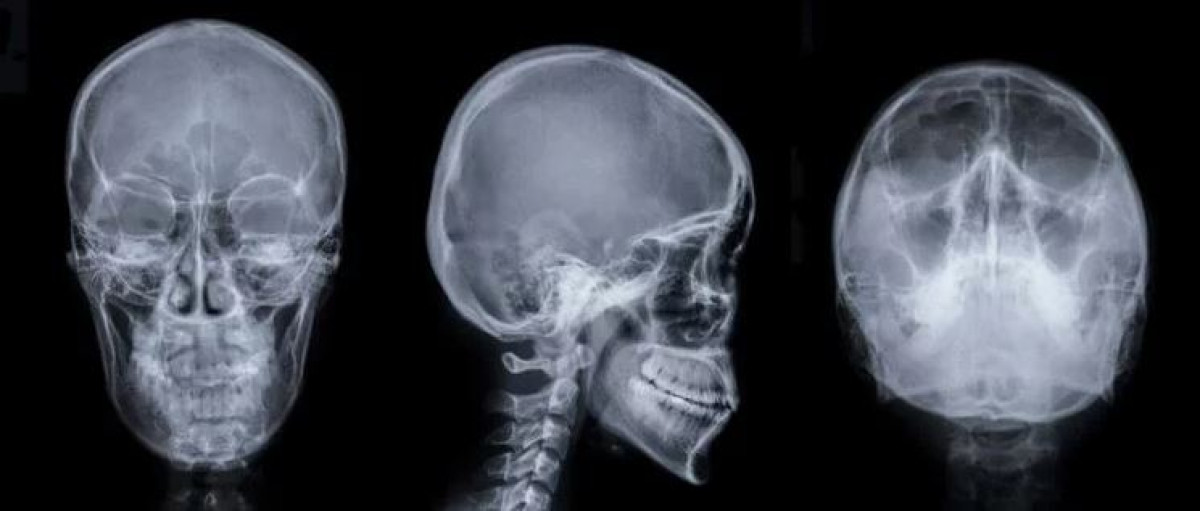

Исследователи считают, что магнитный робот может легко достигать мозга и удалять образовавшиеся в нем сгустки крови. Напомним, что именно нарушения кровообращения в мозге являются причиной инсульта, инфаркта и других смертельных заболеваний. Ранее для устранения подобных проблем хирургам требовалось либо проводить открытую операцию, либо использовать катетеры, за передвижением которых необходимо следить при помощи рентгеновского оборудования.

Врачи, понятное дело, не хотят подвергать себя облучению, поэтому магнитные роботы для проведения таких операций придутся как нельзя кстати. Ими можно управлять дистанционно, например, поставив в операционной роботизированную руку со встроенным магнитом. Хирурги смогут дистанционно управлять магнитным роботом и доводить его до мозга, так же контролируя его движения при помощи рентгена. Но при этом врачи не будут подвергать себя облучению.